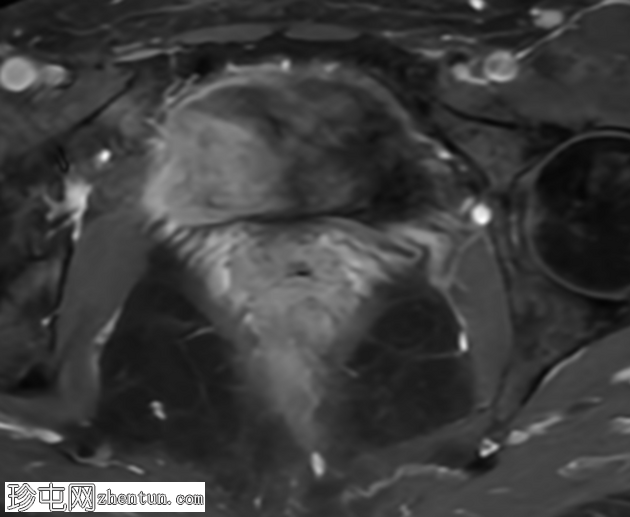

轴位T2加权像

脂肪抑制像

盆腔MRI显示右侧卵巢解剖位置可见一边界清晰的卵圆形肿块。该病灶由囊性和实性成分组成。囊性部分壁薄,在T2加权像上呈均匀高信号,在T1加权脂肪抑制序列上呈低信号,无对比剂增强。该实性成分的信号特征与正常卵巢组织相似,DWI成像未见扩散受限,静脉注射造影剂后未见异常强化。

此外,在子宫左侧壁可见一管状薄壁囊性结构,延伸至同侧髂外血管,末端呈盲端。该结构在T2加权像上呈均匀高信号,在T1加权脂肪抑制序列上呈低信号,且无造影剂强化。

本例中,盆腔MRI显示,患者右侧卵巢解剖位置存在一个边界清晰的附件肿块,该患者有20年前行双侧输卵管卵巢切除术的病史。该病灶包含囊性和实性成分,其中实性部分表现出与正常卵巢组织相似的信号特征。无扩散受限和无可疑的增强扫描强化提示排除恶性病变。这些影像学特征结合相关的手术史进行解读,符合残留卵巢组织的特征,支持卵巢残留综合征的诊断。此外,还发现对侧子宫左侧延伸出一个管状薄壁囊性结构,末端呈盲端。其形态、信号特征和无强化表现符合输卵管残端或输卵管残端积水,这是输卵管切除术后常见的术后表现。附件残余的存在进一步支持术后病因,而非原发性妇科肿瘤